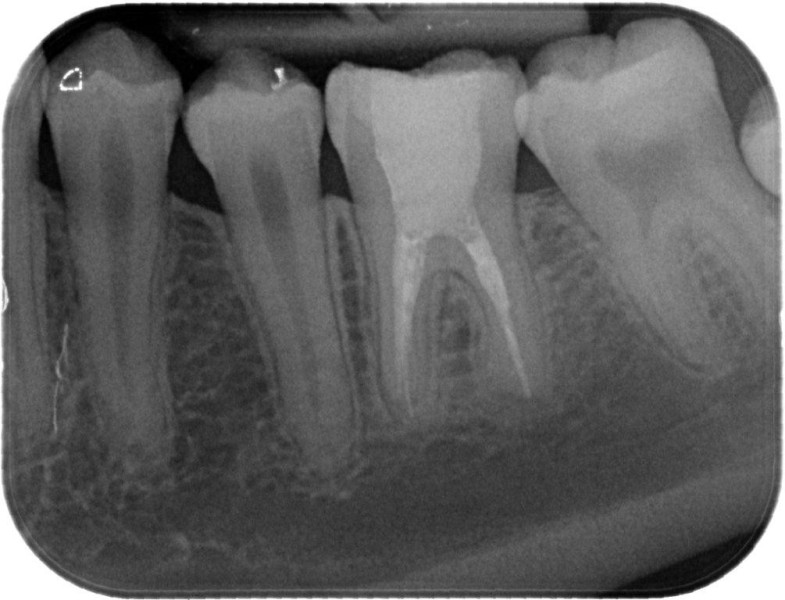

Molar retreatment